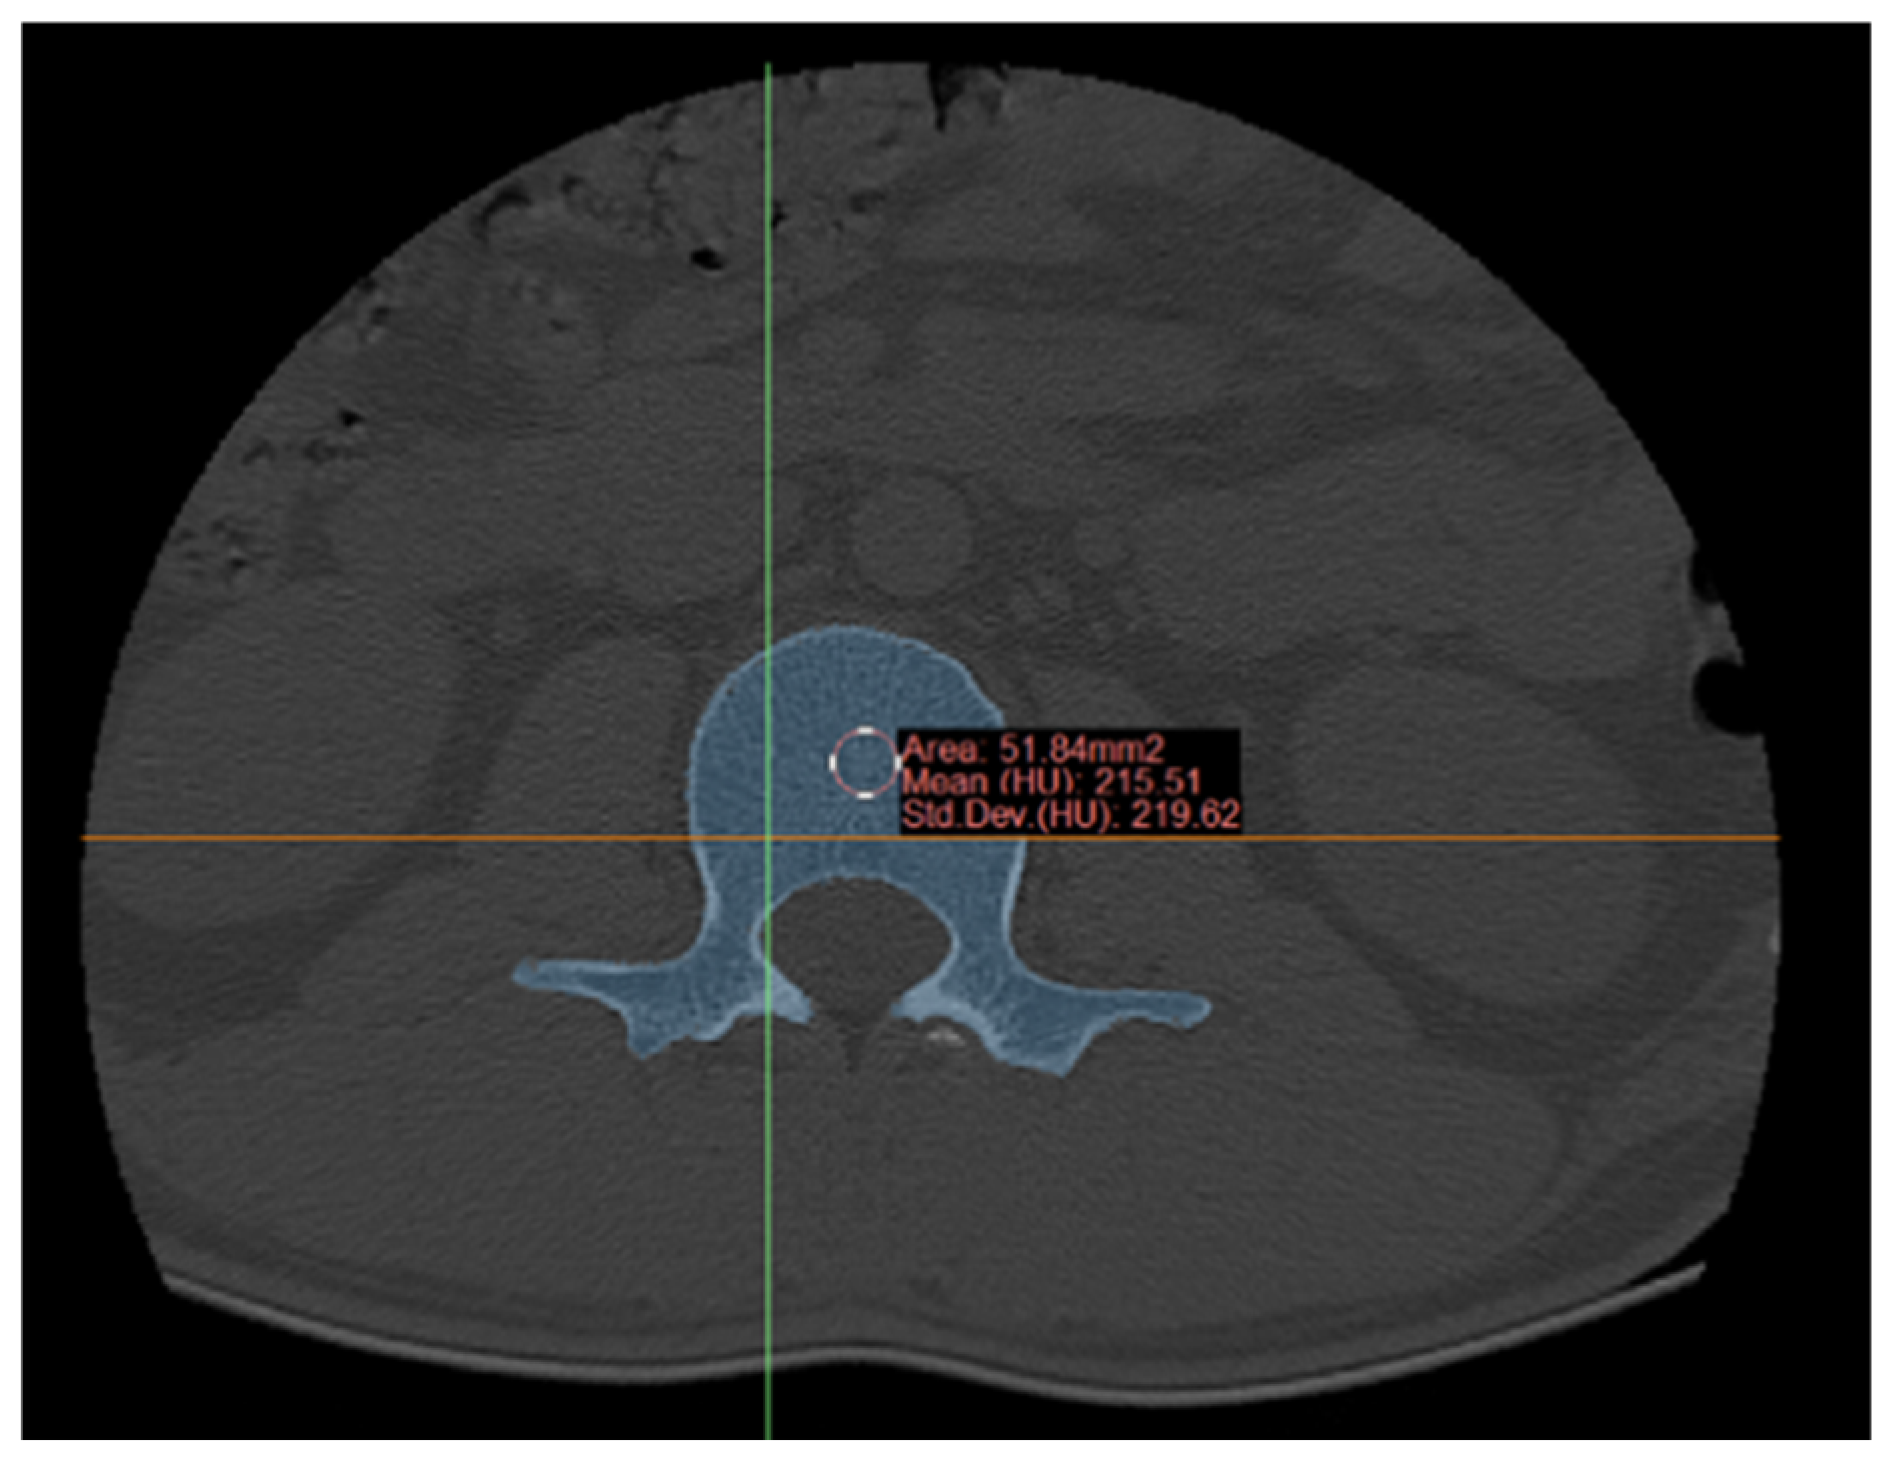

5.2. Bone Density Measurement and 3D Printing

- The construction and preparation of lumbar spine models, including the L4 segment and composite vertebral models suitable for 3D printing: Bone density values derived from CT scans of the L4 segmental lumbar spine were integrated into the GA-BP neural network to determine precise 3D printing parameters, facilitating accurate model preparation.